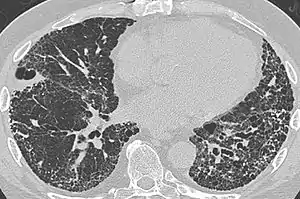

| CT scan of a patient with UIP. There is interstitial thickening, architectural distortion, honeycombing and bronchiectasis. | |

UIP may be diagnosed by a radiologist using computed tomography (CT) scan of the chest, or by a pathologist using tissue obtained by a lung biopsy.

Radiology

Radiologically, the main feature required for a confident diagnosis of UIP is honeycomb change in the periphery and the lower portions (bases) of the lungs.[3]